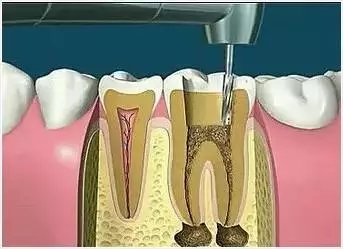

吃藥什麽(me) 的結果不好,隻有到醫院打開牙髓腔,把感染發炎的牙神經取出來,才能起到止痛的作用。這個(ge) 操作叫作殺牙神經,專(zhuan) 業(ye) 的說法是根管治療,在牙神經去除後,需要對牙齒進行消毒殺菌,可能需要多次封藥,治療完善後,沒有疼痛等異常後再把牙齒充填起來。

1.拍片 2.開髓 3.確定根管長度

4.根管預備 5.根管衝(chong) 洗消毒 6.根管充填